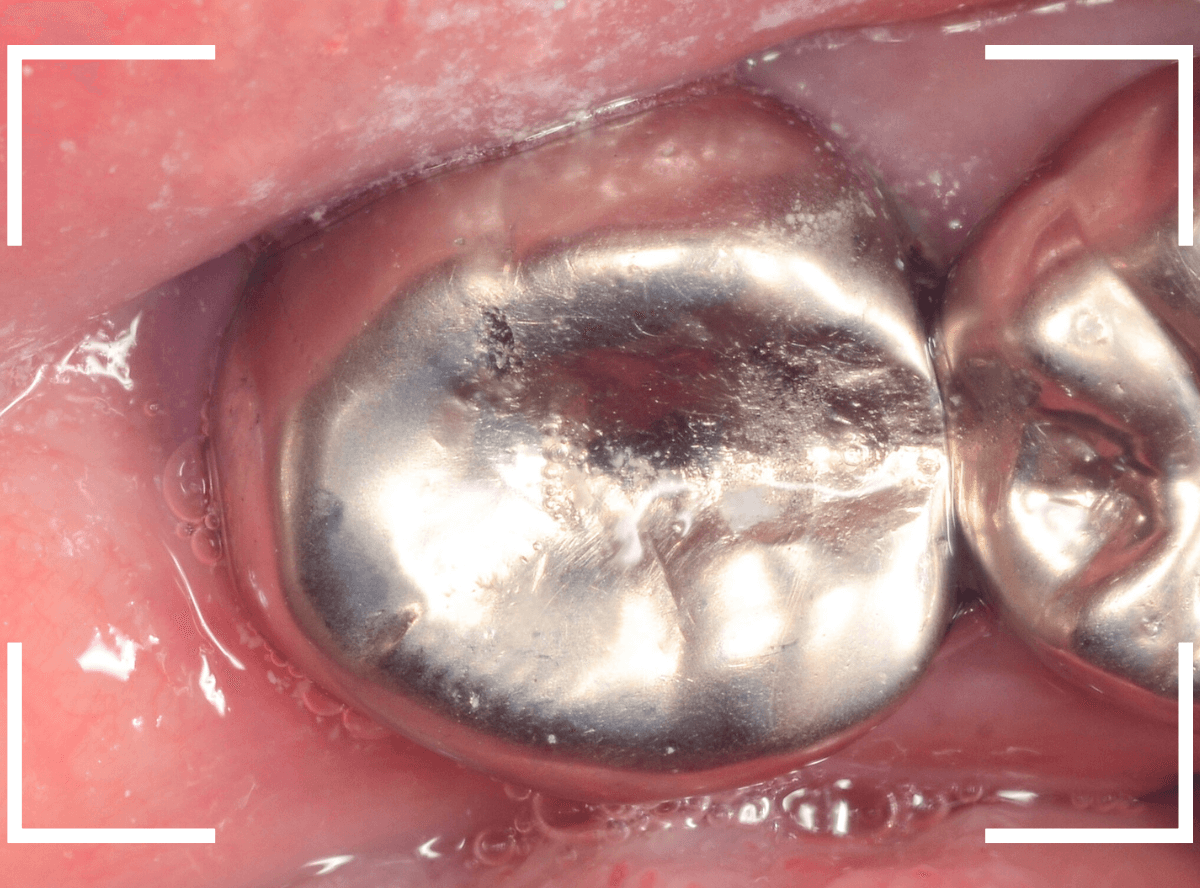

Case.16 <動画編> 痛くなくても、銀歯の中は…

今回は、さし歯の中で虫歯が深く進行してしまった患者さんのケースです。

神経を取った歯のため、痛みは感じませんが、虫歯にならないわけではありません。

さし歯の中で虫歯はどう進行しているのでしょうか。